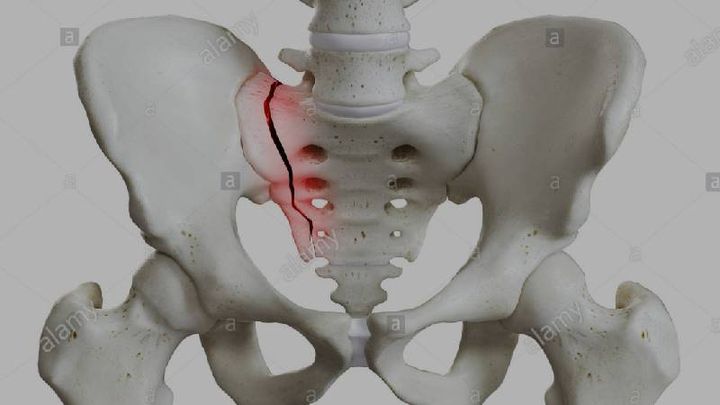

Hey everyone i absolutely hate asking for handouts but im not sure where else to turn. As most of you know I broke my pelvis about a month ago. The medical bills are piling up and i need to pay upfront to see a orthopedic surgeon to make sure it hasnt become displaced and need surgery. Anything you can do to help even just sharing is greatly appreciated.